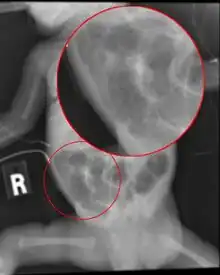

- Necrotizing enterocolitis (most common in premature infants)